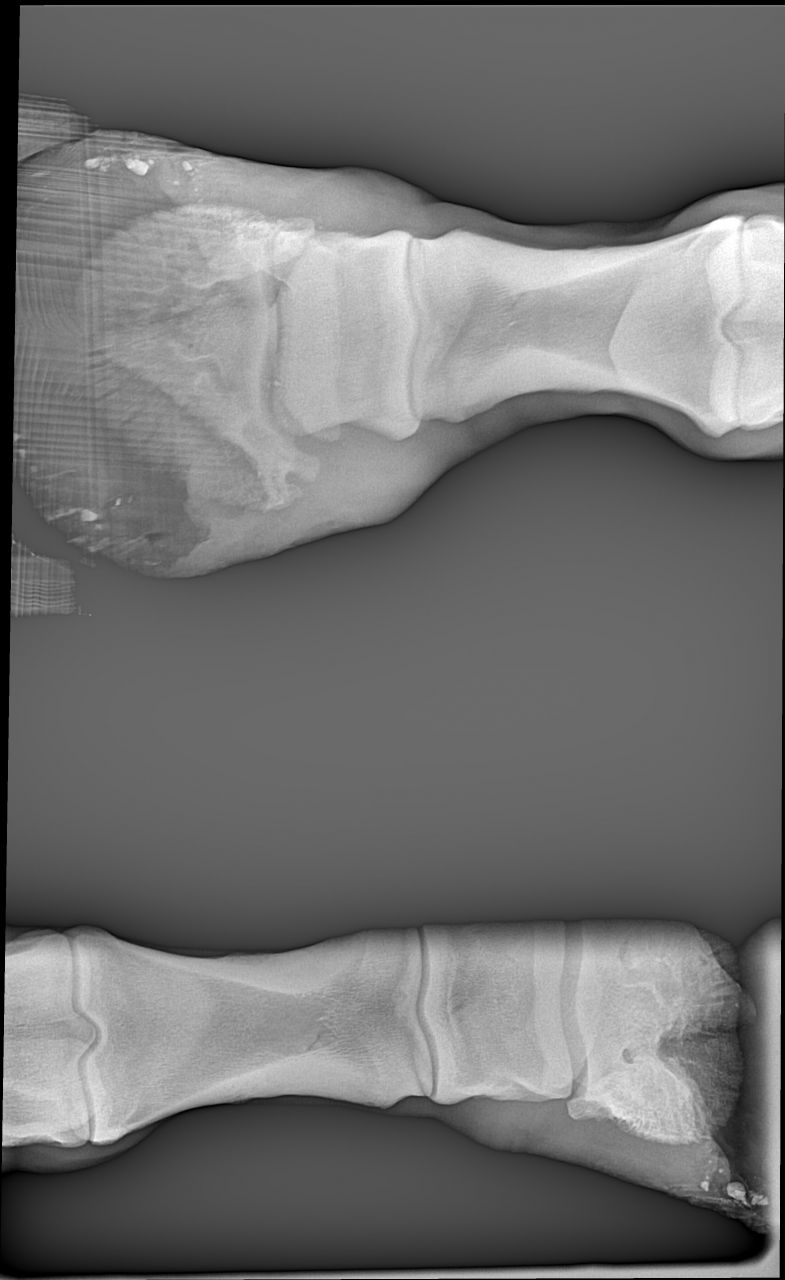

| Dire merci | Voici les premières radios de mon cheval de sa maladie antérieur droit ![]() ![]() |

| Dire merci | premieres radios antérieurs gauche![]() ![]() ![]() |

| Dire merci | les premières radios sont de juillet 2012 Voici les radios de l'antérieur droit fin septembre 2012 ![]() et celles de l'antérieur gauche ![]() ![]() |